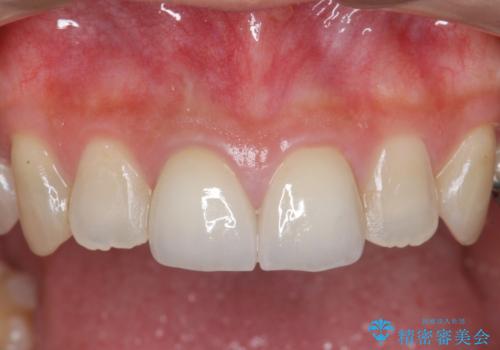

- 26.4万円(仮歯×2・ファイバーコア・ジルコニアクラウン×2)費用は治療当時の料金となります

虫歯の徹底的な除去、根管治療を行いセラミック治療に入る前の環境をしっかりと整えたのち審美的なジルコニアセラミックで治療を仕上げました。